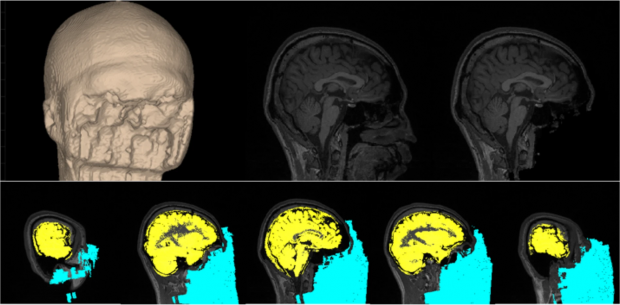

일본 국제전기통신기초기술연구소(ATR) 등 국제연구진은 데크네프(DecNef)라고도 불리는 이 기술에 대한 연구 성과를 발표했다고 영국 일간 데일리메일 등 외신이 25일자로 전했다.

예를 들어 거미 공포증이 있는 한 사람이 타란툴라의 모습이 담긴 사진을 보면 뇌에서는 특정 방식으로 반응이 일어나고 이는 컴퓨터에 기록된다. 이후 연구진은 참가자의 뇌에서 두려움을 유발하는 반응이 일어날 때마다 금전적 혜택을 제공했다.

그 결과 이런 긍정적인 강화가 이 사람이 다시 거미 사진을 봤을 때 뇌에서 기존 방식으로 반응이 일어나지 않도록 뇌를 무의식적으로 변하게 하는 것으로 나타났다.

연구 공동저자인 ATR의 미쓰오 가와토 박사는 “패턴이 감지될 때마다 반복적으로 보상을 주는 간단한 작용은 원래 기억이나 정신 상태를 수정한다”면서 “중요한 점은 참가자들이 패턴을 인식할 필요가 없다는 데 있다”고 설명했다.

연구 주저자인 ATR의 아우렐리오 코르테스 박사도 “데크네프라는 접근 방식은 기존 치료 방법보다 임상 집단에 큰 혜택을 줄 수 있다. 환자들은 노출 치료와 관련한 스트레스나 기존 약물에 의한 부작용을 피할 수 있다”면서 “따라서 이 기술의 개발을 가속화하는 것이 중요하다”고 지적했다.